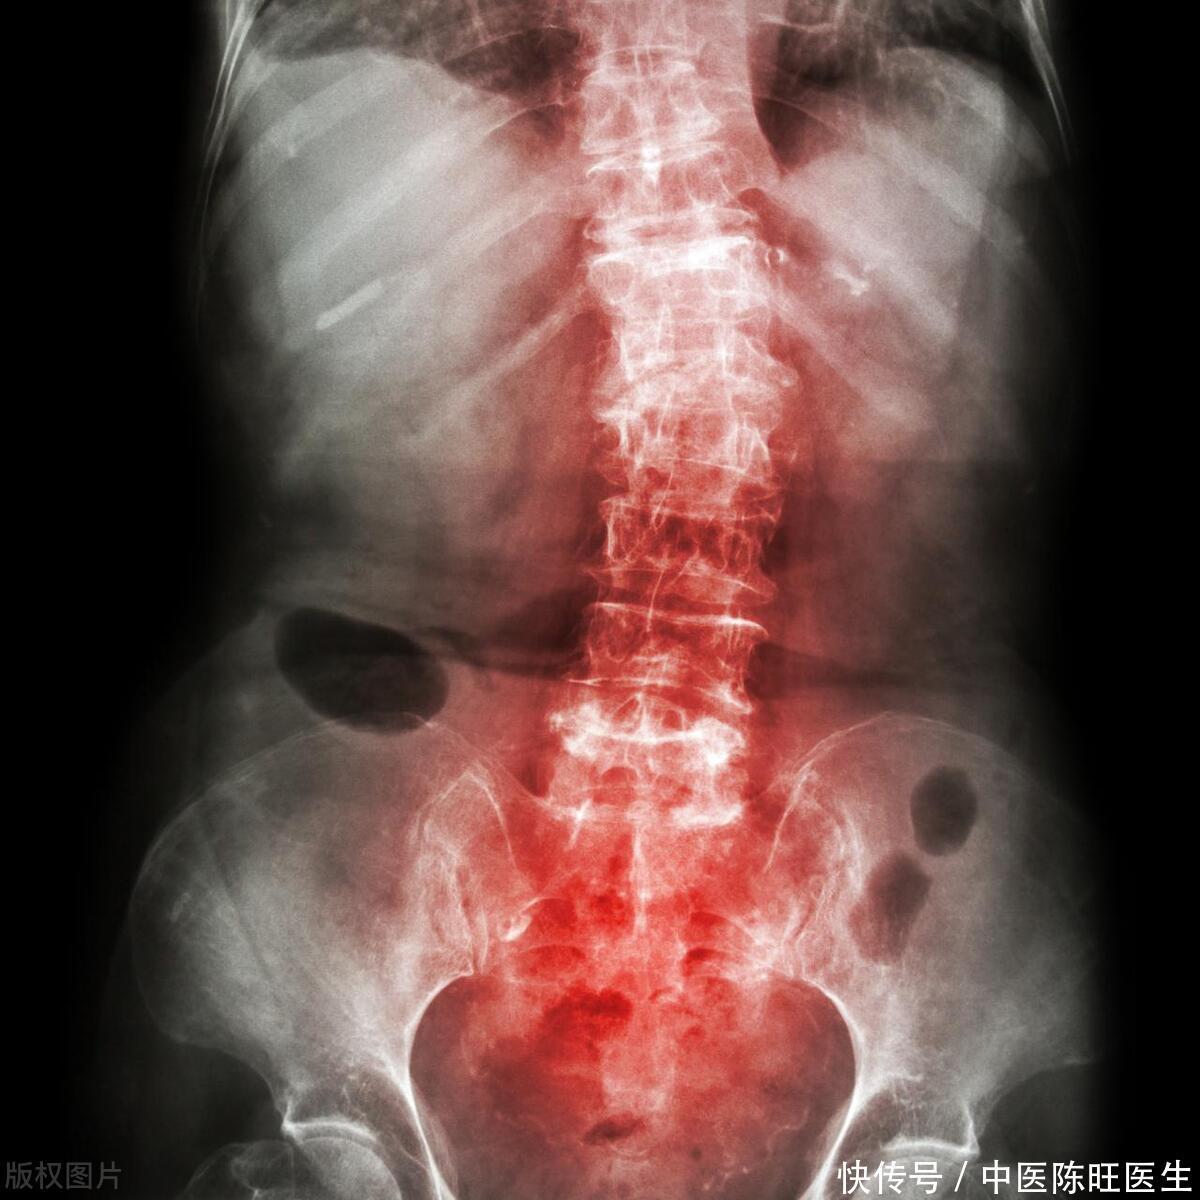

家人的关怀与担忧促使小陈最终踏入了医院的门槛。经过详尽的医学检测,医生揭示了真相,原来小陈的后背疼痛源于一种名为“强直性脊柱炎”的病症。这种病在年轻人中并不罕见,但如果不及时治疗,可能会导致脊柱畸形、关节僵硬等严重后果。

如果你的后背疼痛持续不断,且痛感剧烈,尤其是在夜间或休息时更为明显,那么这可能是脊柱骨折、腰椎间盘突出等严重疾病的信号。若对这些疾病置之不理,它们可能悄然侵袭神经系统,造成无法挽回的损害。

当背痛症状与发热、寒战、体重减轻等共现时,它们或许是感染、炎症乃至肿瘤等潜在病况的警示信号。举例而言,诸如脊柱结核、强直性脊柱炎等疾患,均可能诱发背部疼痛,并伴随一系列不适之症。

3. 疼痛部位特殊

如果你的后背疼痛集中在某个特定区域,如肩胛骨中间区域或脊柱两侧等,那么这可能是某些特定疾病的信号。例如,心梗患者的后背疼痛通常会向左肩和左臂放射;主动脉夹层患者的后背疼痛则可能伴有剧烈的胸痛和高血压等症状。